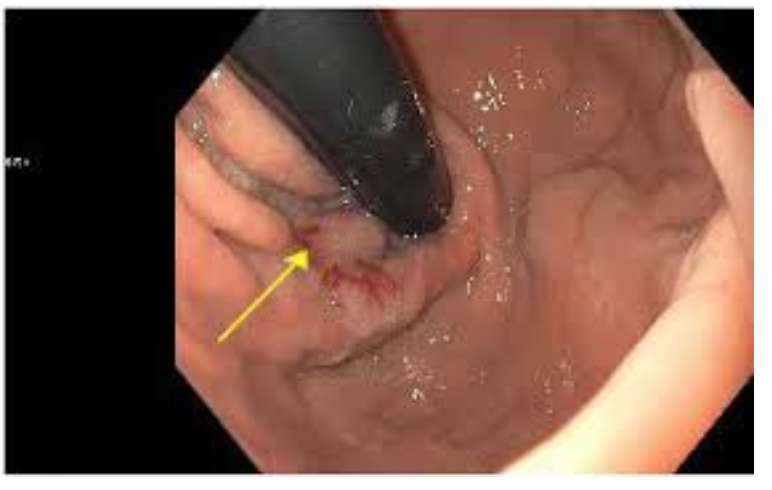

Dieulafoy lesion